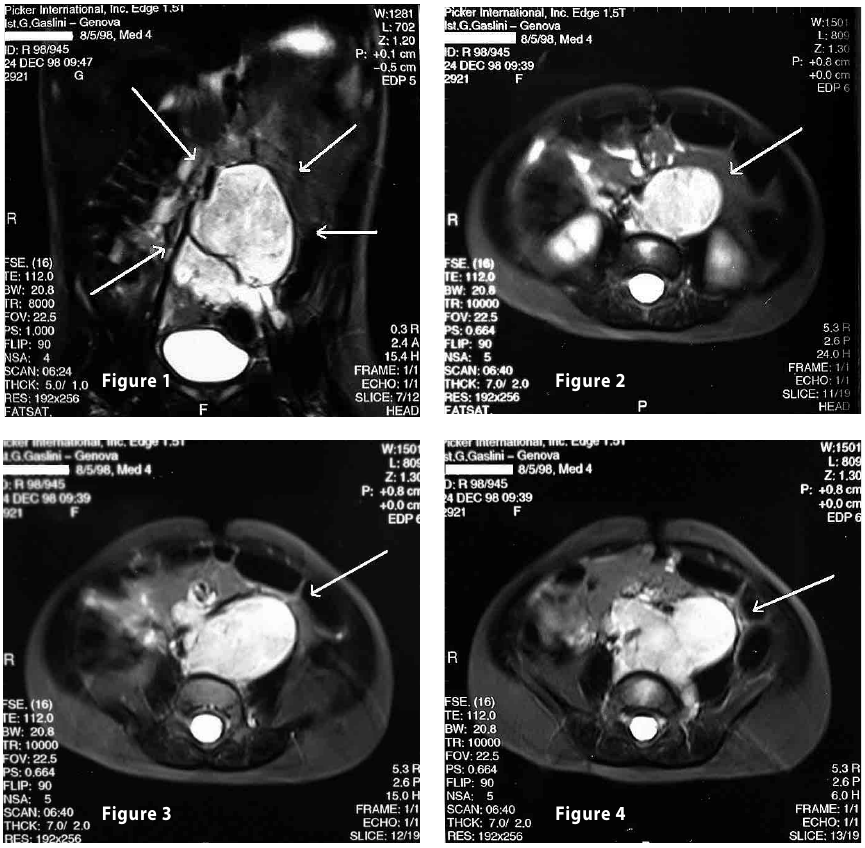

Complete objective response of neuroblastoma to biological treatment.

Figure1

Figure2

Figure3

Figure4

Figure1-2

Figure3-4

Figure1-2-3-4